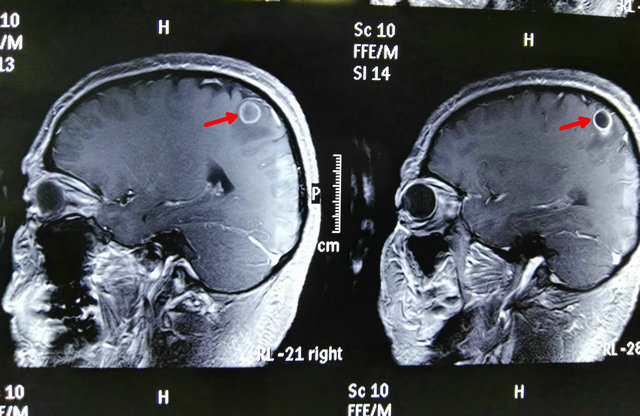

患者李先生今年35岁,一个月前发现左手拿东西不稳了,并且还伴有麻木症状,在多次求医无果后来到郑州大学五附院神经外科一病区。医生经过仔细检查后给李先生诊断为右侧顶叶(中央后回)占位性病变(图1、2)。该病变所处部位十分重要,周围神经、血管复杂,且病变较小,如果术中定位不准,可能会增加副损伤,若稍有不慎可能导致患者偏瘫。

图1

图2